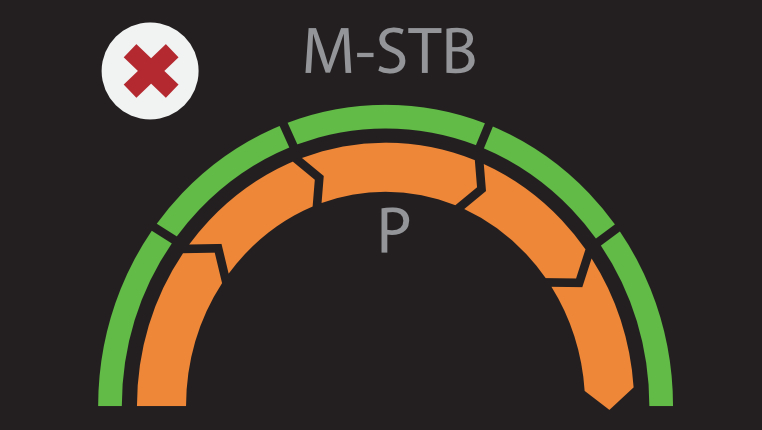

VÃĄrias solu??es de ultrassom*

â Sonda de ultrassom profissional para facilitar o exame de ascite, etc.

â Pun??o guiada por ultrassom dedicado para aprimorar a precis?o das biÃģpsias

â A excelente qualidade de imagem e as fun??es de ultrassom permitem uma avalia??o abrangente da morfologia e hemodin?mica do fÃgado.

â Pun??o guiada por ultrassom dedicado para aprimorar a precis?o das biÃģpsias

â A excelente qualidade de imagem e as fun??es de ultrassom permitem uma avalia??o abrangente da morfologia e hemodin?mica do fÃgado.

* DisponÃvel no Hepatus 6